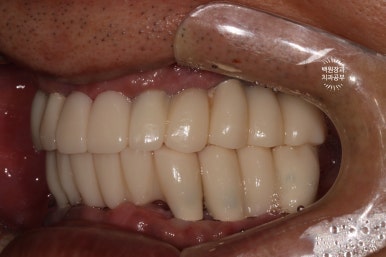

맞춤형 지대주를 연결하고 임시치아를 장착한 모습입니다!

사실 완벽하지는 않습니다만, 이렇게 제작을 해드리면 드디어... 씹는 연습을 해보실 수 있게 됩니다.

여기까지 오기까지 이를 뽑고 나서부터 약 6개월의 시간이 흘렀네요...

치아의 모양과 크기를 평가해보실 수 있고, 혀나 볼이 씹히지 않는 등을 확인할 수 있습니다.

이렇게 임시치아만 제작되어도, 이제 임시틀니를 사용하지 않아도 되기에 바로! 밝게 웃는 환자분의 얼굴을 볼 수 있다는 것 ~~ 그것이 치과의사로 사는 보람 아니겠습니까 ^^